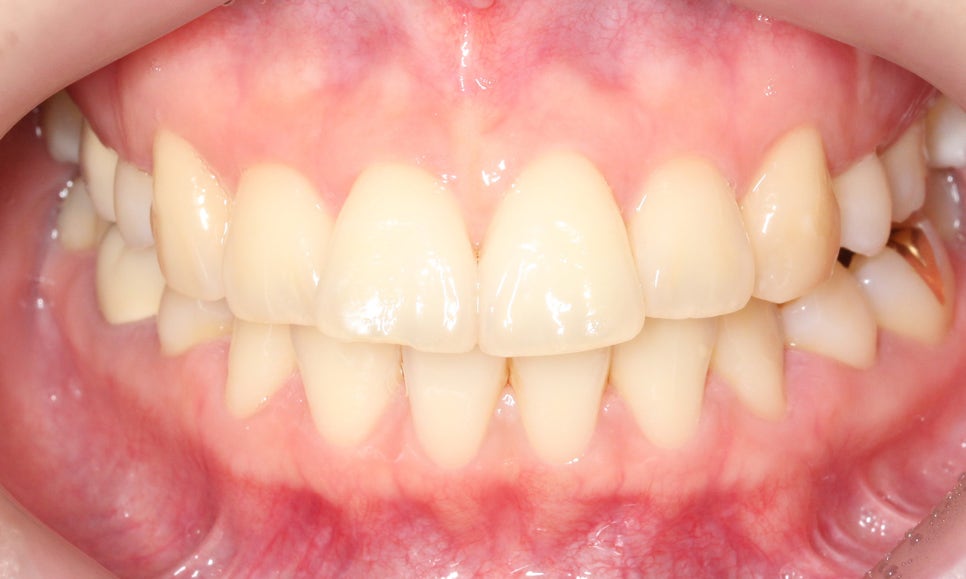

대치동치과 돌출입 교정 전 모습입니다.

전치부의 치아 배열을 보면

앞니가 튀어나와 있고 상하악의

정중선이 변위된 모습을 확인할 수 있는데요,

치아의 중심이 잘 맞지 않는 경우

어금니 부분이 어긋나게 교합되거나

턱 부분의 교합이 좋지 않은 상황일 수 있습니다.